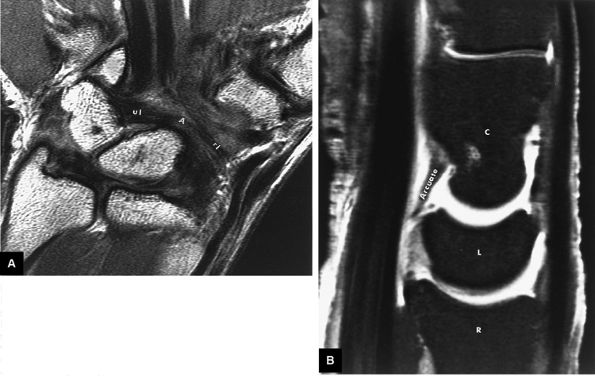

FIGURE 10.75 ● The arcuate or deltoid ligament. (A) The ulnar limb (ul) and radial limb (rl) of the volar intrinsic arcuate ligament are shown in the same volar plane on a T1-weighted coronal image. Both limbs attach centrally to the capitate. (B) The arcuate ligament is shown between the capitate (C) and lunate (L) on a midsagittal FS T1-weighted arthrogram. The ulnar limb of the arcuate or deltoid ligament is the capitoscaphoid arm, and the radial limb of the arcuate ligament is the capitotriquetral arm.

|